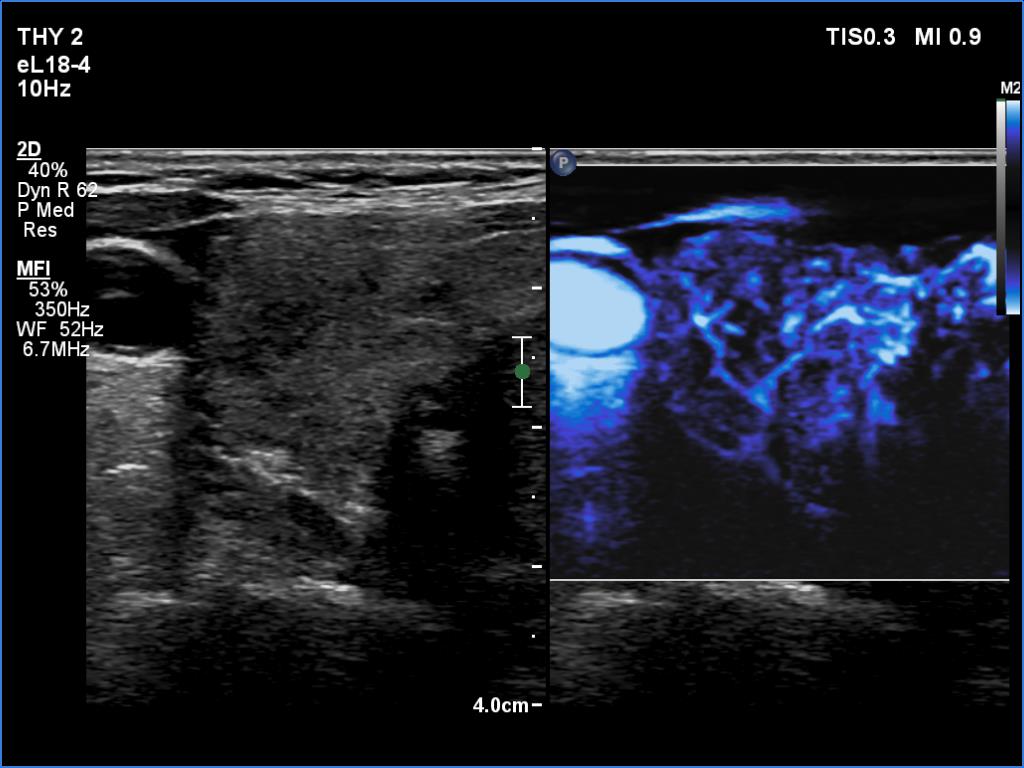

Clinical presentation: A 66-year-old woman was referred for cytology. The patient felt discomfort in her neck while lying on her left side for a few months.

Palpation: a firm nodule in the left lobe.

Diagnosis: Hashimoto's thyroiditis. Suspicion of follicular cancer.

Frozen section disclosed follicular cancer, therefore total thyroidectomy was performed. The definitive histopathological diagnosis was widely invasive follicular cancer and Hashimoto's thyroiditis.